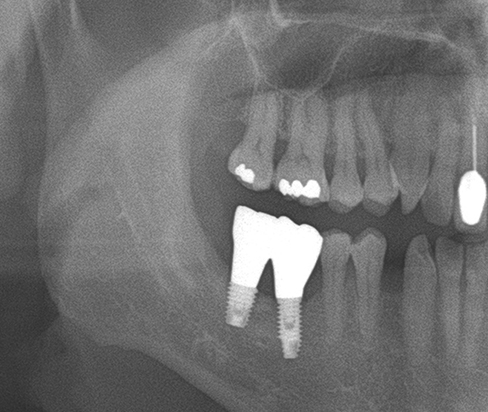

• A clinical case using resorbable membrane 2